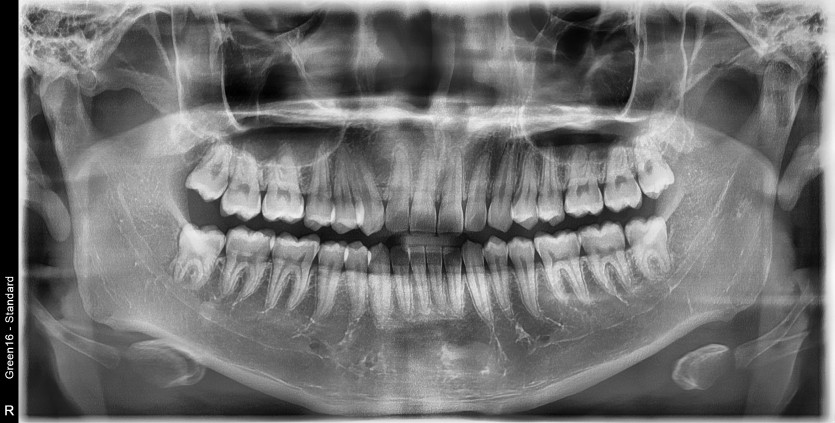

#18,48 사랑니 발치

구강외과 전문의가 당일 발치했습니다.